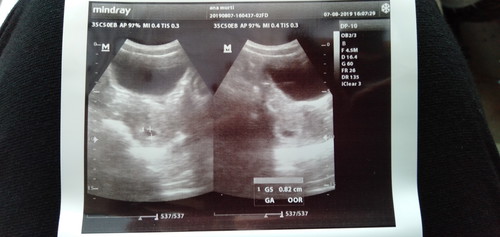

Assalamualaikum mau tanya disini ada ga yg ngalamin waktu usg GA nya (Usia Kandungan) ga terdeteksi? kalo dokter bilang udah 7 minggu tpi pas usg janin masih kecil banget dan GA = 00

Iya bun, aku USG 6 minggu masih kantong, alhmdllh 9 minggu USG detak jantung janin sudah kencang